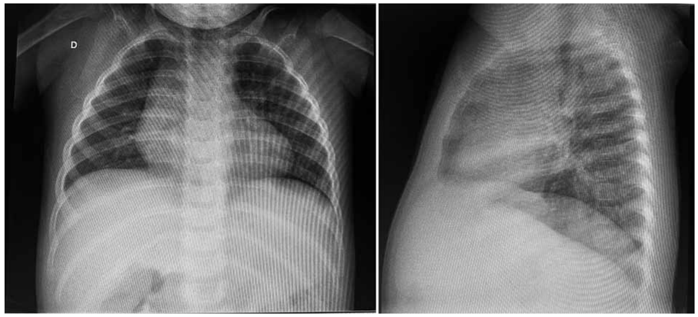

A figura a seguir apresenta a radiografia de tórax dessa paciente:

(Arquivo pessoal; imagem usada com autorização)

Nesse caso, a hipótese diagnóstica e a conduta corretas são, respectivamente: